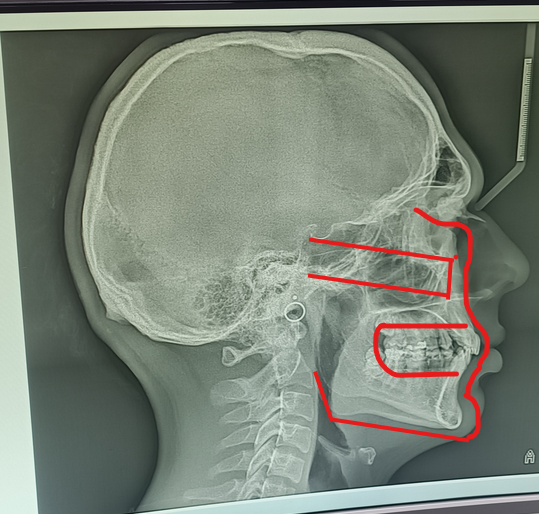

So how recessed is my maxilla?or it's not?it's worse not gonna lie

It lacks both superior growth and forward growth. Also severe recession in the nasal area, i honestly feel so bad that i dont even wanna ask for solution

it's beyond recessed g, pointed out some flaws and where they should beSo how recessed is my maxilla?or it's not?